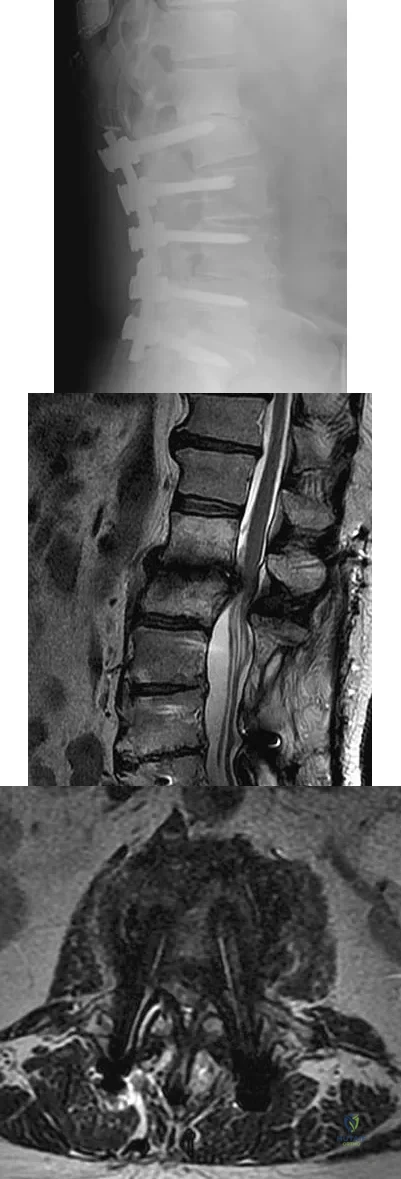

Question 48

An otherwise healthy 54-year-old man who underwent a successful multilevel lumbar decompression and fusion 4 years ago now reports increasingly severe bilateral thigh claudication with paresthesia and severe back pain for the past 12 months. Physical therapy, bracing, and epidural steroids have failed to provide relief. A radiograph and MRI scans are shown in Figures 15a through 15c. He is afebrile, and laboratory studies show an erythrocyte sedimentation rate of 5 mm/h and a normal WBC count. What is the best course of action?

Explanation